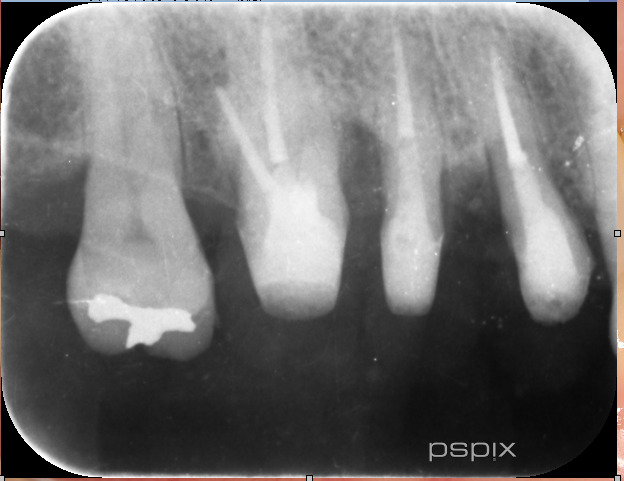

そして1年後

骨の再生が見られます!

歯の揺れも落ち着きました。歯周ポケットも3mmまで回復。